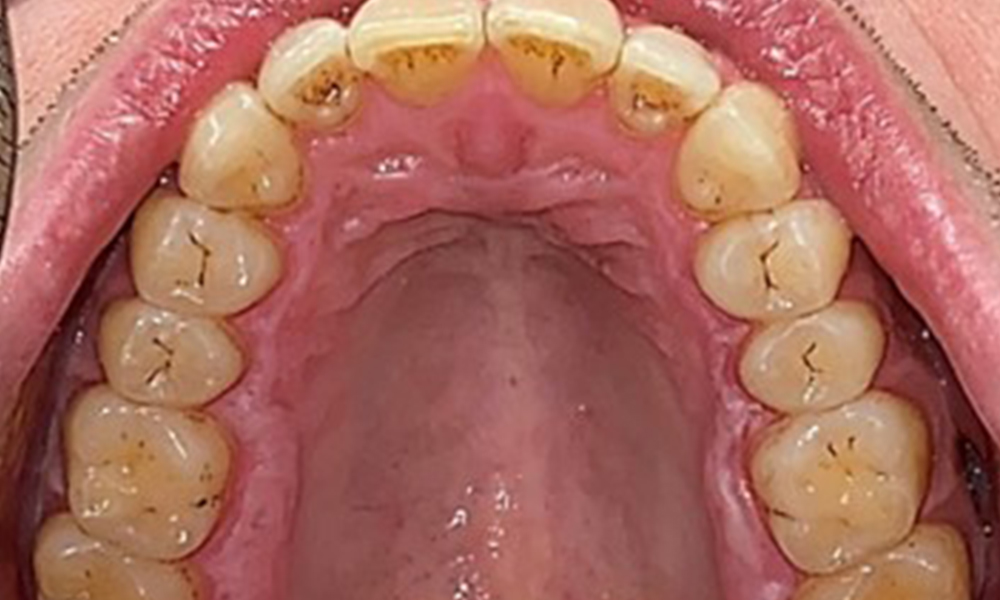

Vue occlusale du maxillaire.

Fig. 3: Vue occlusale du maxillaire, © Dr R. Krapf

Vue occlusale de la mandibule.

Fig. 4: Vue occlusale de la mandibule, © Dr R. Krapf

Il n'y a pas eu de résultats pathologiques extra-oraux. Lors de l'examen intrabuccal, l'inspection de la vue frontale a révélé une décoloration brunâtre près de la gencive kératinisée et à la transition vers la muqueuse mobile (Fig. 2), qui pourrait être attribuée à la consommation de nicotine. Des lésions blanchâtres de la muqueuse ont été observées sur le palais, en particulier près des surfaces palatines des molaires maxillaires, ce qui indique une kératinisation accrue et peut également être attribué à la consommation de nicotine. La langue était recouverte d'un enduit amovible blanc et brunâtre.

Résultats dentaires

Le patient a une dentition complète avec un total de 28 dents. Il y avait des érosions et des attritions notables. (Fig. 4, Fig. 5). En raison du bruxisme, le patient a porté pendant de nombreuses années une attelle avec une gouttière ajustée la nuit. Les érosions ont été causées par une consommation prolongée de boissons isotoniques. Aucune perte d'os parodontal ou carie active n'a été observée.